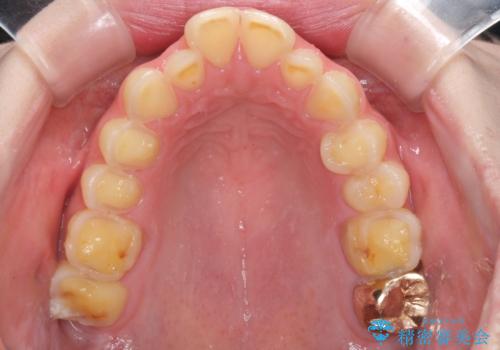

- 一時期の拒食症に伴い歯が酸で溶けてボロボロになってしまったとのことで来院された患者様です。

酸によりエナメル質の大半が溶けており、下顎前歯以外は酷いむし歯のような状態でした。

当初はほとんどの歯をむし歯治療のようにオールセラミッククラウンにて補綴治療を行う予定でしたが、仮歯に置き換えた時点で、口元の突出感や下顎前歯の叢生が気になるとのことで、上下左右の第一小臼歯4本を抜歯したワイヤー装置での抜歯矯正を行うこととしました。

矯正治療終了後に、残った歯をオールセラミッククラウンにて補綴治療を行うこととしました。